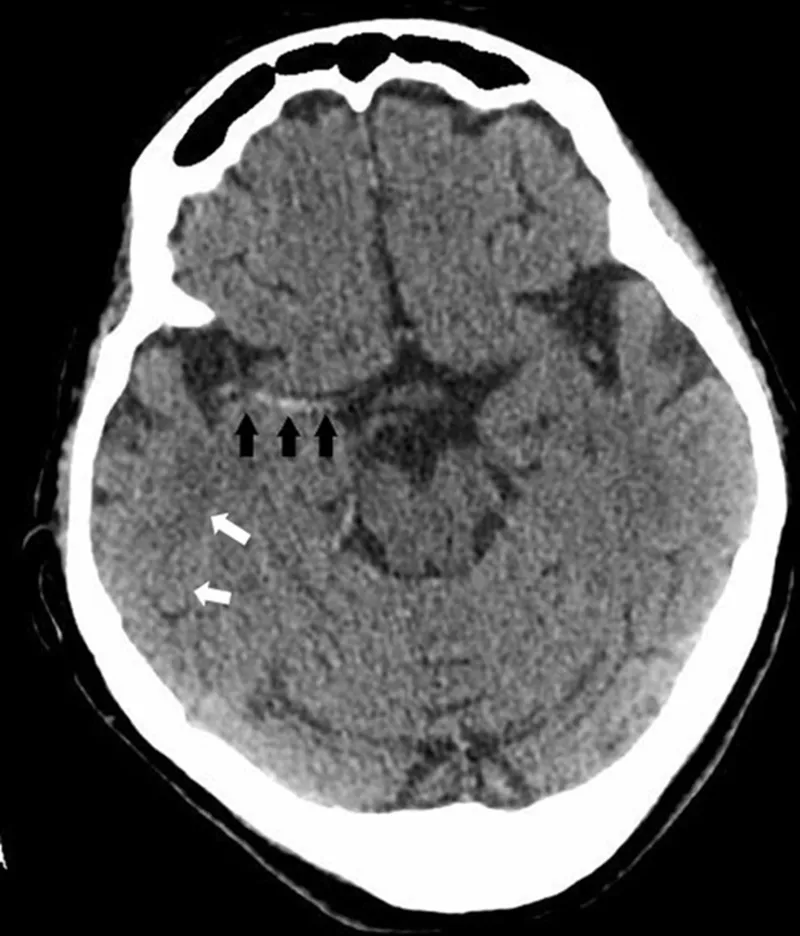

Primary Goal: Immediate non-contrast CT (NCCT) to rapidly exclude intracranial hemorrhage (ICH) before thrombolysis. Ischemic changes may not be visible in the first few hours.

Key NCCT Findings:

- Hemorrhage: Appears hyperdense (bright).

- Early Ischemia: Subtle signs like loss of grey-white differentiation, the insular ribbon sign, or a hyperdense MCA sign.

⭐ The ASPECTS score on NCCT quantifies early ischemic changes in the MCA territory. A score < 6 suggests a large, established infarct and may be a relative contraindication for thrombectomy.